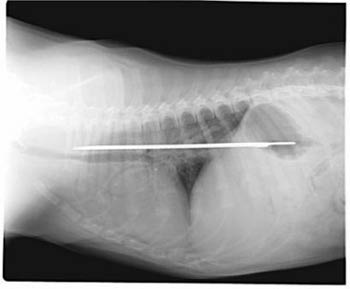

This photo of an X-Ray provided by Imperial Point Animal Hospital in Fort Lauderdale, Fla., Saturday, Sept. 24, 2005, shows a 13-inch serrated knife that somehow was swallowed by 'Elsie' a 6-month-old Saint Bernard puppy. [AP] |

Elsie, a Saint Bernard puppy, apparently had the blade between her esophagus and stomach for about four days before it was removed earlier this week in a 2-hour operation.